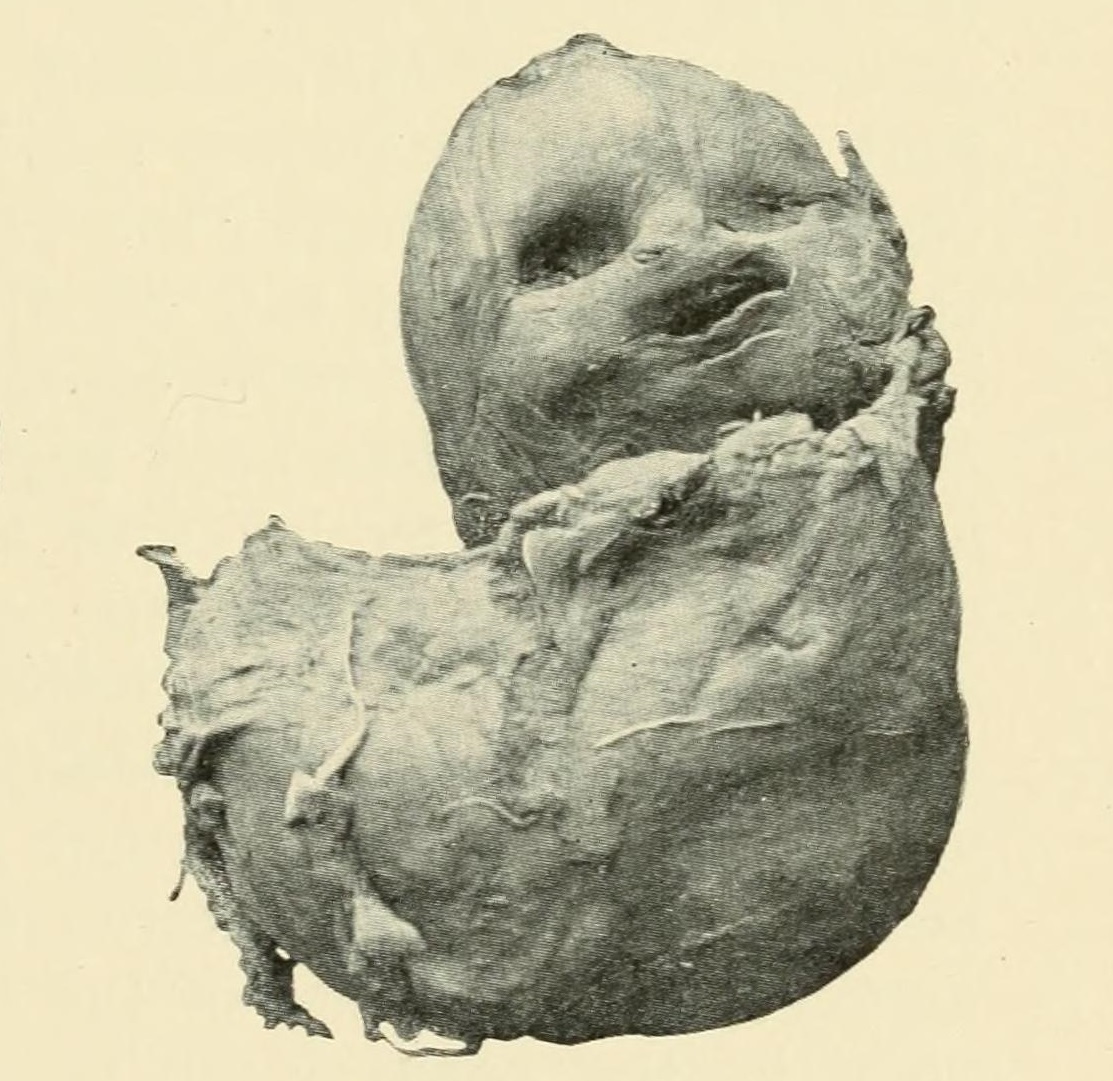

Foto: Barton Cooke Hirst, Public domain, via Wikimedia Commons

Foto: JG Clark, Public domain, via Wikimedia Commons